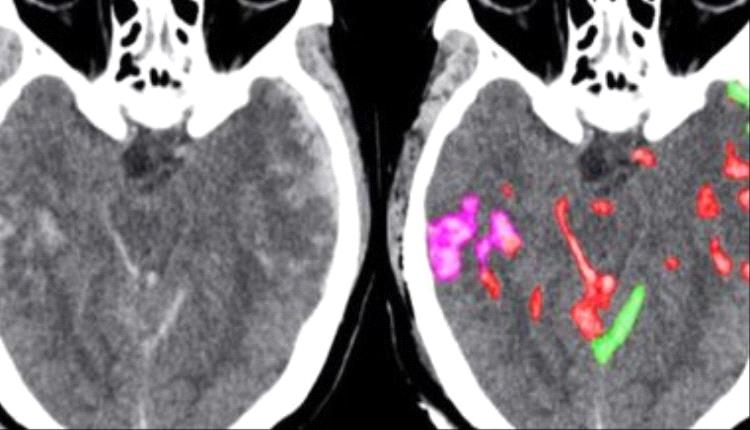

علامات وأعراض النزيف الداخلى